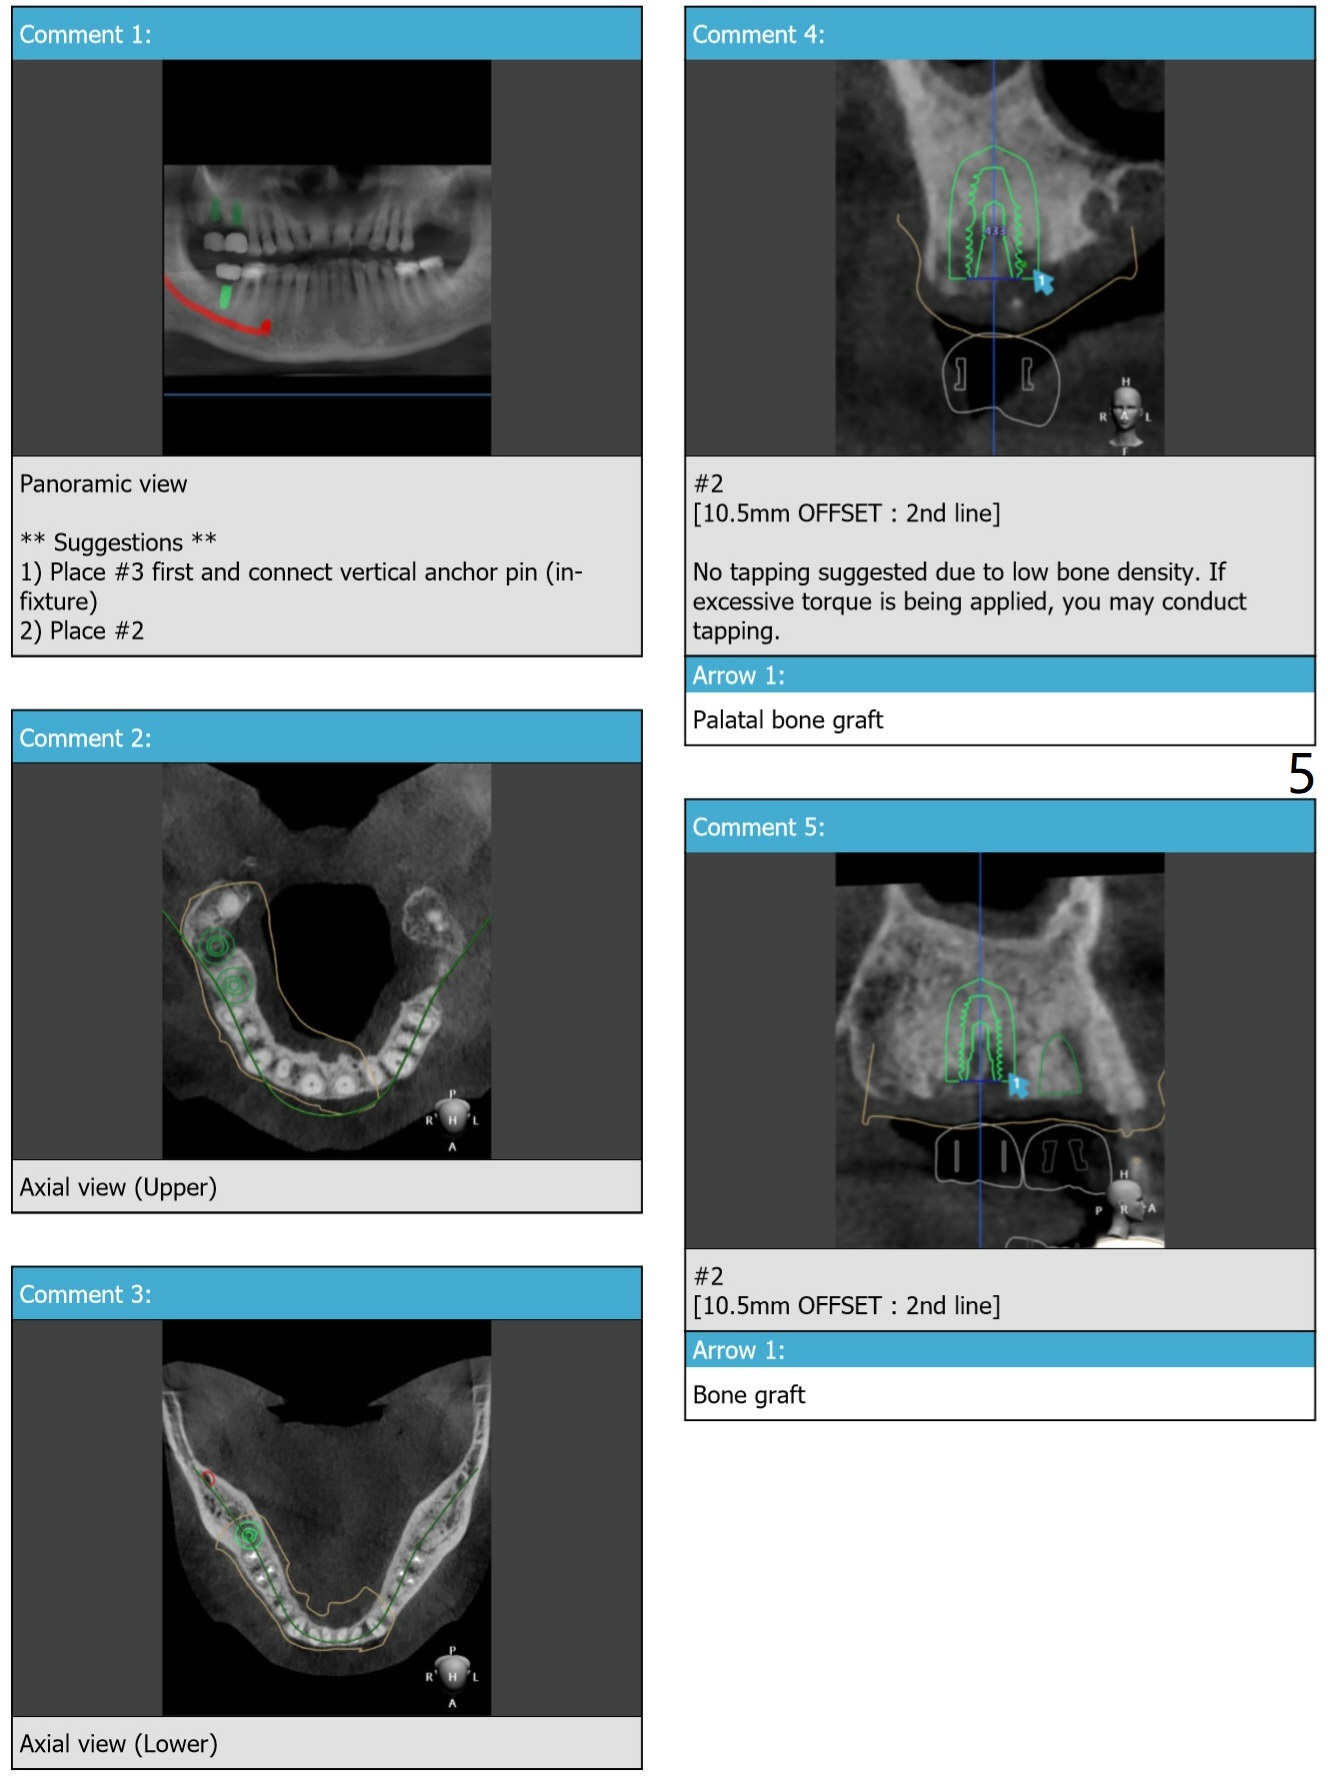

Three Implants On the Right M

A 65-year-old man agrees to have #2,3,31 implants placed following those of #14,15 (Fig.1).